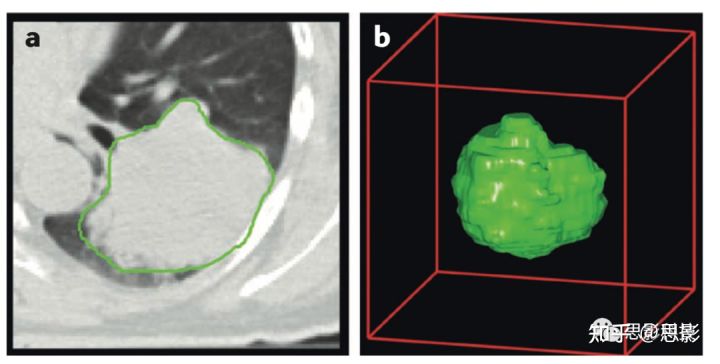

为了比较不同软件实现影像组学特征提取的算法,我们举了一个例子,其中CT获得的四名肺癌患者的原发肿瘤区域和相应肿瘤轮廓的数据作为“真实”数字模型(图3)。利用预处理后的图像数据,我们计算了一组常用的特征,以作为特征数据集参考。

图3,影像组学体模数据

a,数字体模CT图像的代表性图像,肿瘤轮廓显示为绿色。

b,肿瘤区域的3D渲染。